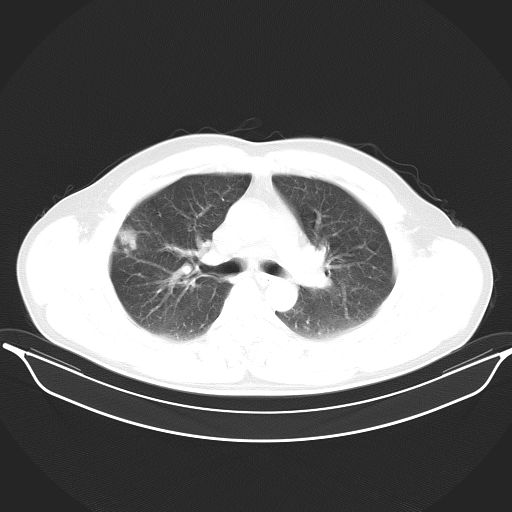

标题: CT25490:男,40岁,体检发现;无其它不适。 [打印本页]

标题: CT25490:男,40岁,体检发现;无其它不适。

考虑右下肺周围性肺癌并肺内多发转移,纵隔淋巴结转移!

支持 !考虑右下肺周围性肺癌并肺内多发转移,纵隔淋巴结转移,(气管前腔静脉后,隆突下,主动脉弓下都有了)